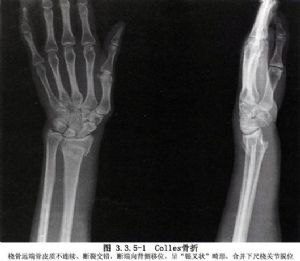

科雷骨折

着地而引起的桡骨下端骨折,称为伸直型骨折,又称科雷骨折(colles骨折)

桡骨远端骨折为最常见的骨折之一,它包括科雷骨折(colle′s fracture)

科雷骨折畸形愈合,严重者桡骨下端关节面极度背倾,桡骨短缩,下尺桡